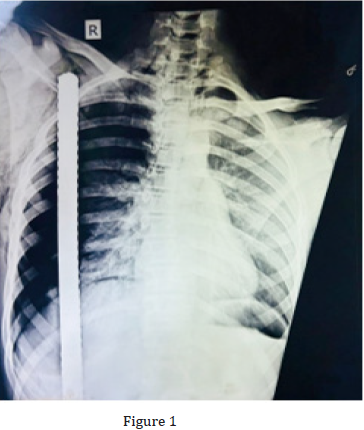

A 17-year-old male suffered an impalement injury with a large iron rod when the vehicle he was driving, fell over a construction site. It was a through and through penetrating injury over his right hemithorax and back. The iron bar pierced the right flank region and was seen coming out through the right chest wall. The patient was immediately rushed to the local hospital where initial resuscitation was done and then patient was referred to AIIMS Rishikesh for definitive management. On presentation, patient was evaluated as per ATLS protocol and following findings were noted. His airway was patent, and he was breathing spontaneously and maintaining SpO2 of 98% on 5lit/min oxygen support via face mask with right sided ICD in situ. On further examination, his right chest wall movement was found to be absent and there was diminished breath over right lung field. However, patient was hemodynamically stable, and rest of the primary survey was normal. A CXR was done in the previous hospital when patient arrived, and it showed the metallic bar traversing through the right hemithorax (Figure 2). Patient was in left lateral decubitus position due the impaling rod and was unable to change his position (Figure 1).